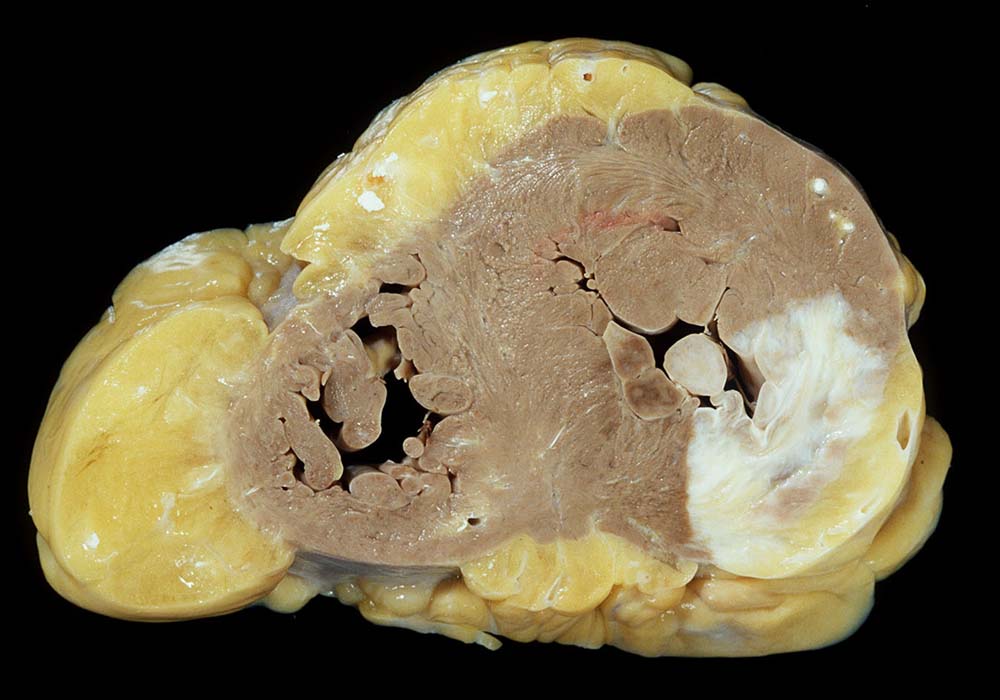

Eine restitutio ad integrum nach abgelaufener Myokardnekrose ist nicht möglich. Wird das Ischämieereignis überlebt, kommt es zu einer reparativen Regeneration mit Ersatz der Muskulatur durch kollagenreiches Narbengewebe. Dieser Vorgang setzt etwa ab dem 9. Tag nach Infarkt ein und dauert bis zur vollständigen narbigen Ausheilung bei transmuralem Infarkt etwa 50 Tage. Makroskopisch imponiert die Narbe als fasriges weisses derbes Areal. Von einem Infarkt spricht man, wenn die Nekroseareale einen Durchmesser von mindestens 3cm Durchmesser haben. Ab dieser Grösse kann klinisch das Bild eines Myokardinfarktes ausgelöst werden. Kleinere, makroskopisch sichtbare Narben werden als grobfleckige Myokardfibrose (> 873) (> 234) bezeichnet.

Im Bereich grösserer Narben ist das Myokard verdünnt. Bei 8% der transmuralen Infarkte entsteht im Bereich der Narbe ein Herzwandaneurysma (> 2088) mit oder ohne wandständige Thrombose (> 348). In 5-15% führen die Thromben zu systemischen Embolien. Von der Randzone der Aneurysmen gehen oft hartnäckige ventrikuläre Rhythmusstörungen aus. Grosse Narben führen zu einer Verminderung der Pumpleistung mit Herzinsuffizienz.